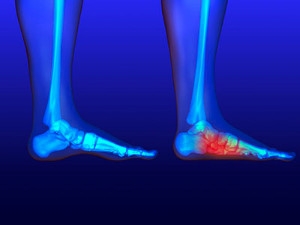

What to Know About a Broken Toe

Trauma to the foot, especially the toes, can occur in many ways. Banging them, stubbing them, or dropping something on them are a few different ways this trauma can occur. Given the fact that toes are positioned in front of the feet, they typically sustain the brunt of such trauma. When trauma occurs to a toe, the result can be a painful break or fracture. Another type of trauma that can break a toe is repeated activity that places stress on the toe for prolonged periods of time.

Broken toes can be categorized as either minor or severe fractures. Symptoms of minor toe fractures include throbbing pain, swelling, bruising on the skin and toenail, and the inability to move the toe with ease. Severe toe fractures require medical attention and are indicated when the broken toe appears crooked or disfigured, when there is tingling or numbness in the toe, or when there is an open, bleeding wound present on the toe.

Generally, a minor toe break will heal without long-term complications. However, it is important to discontinue activities that put pressure on the toe. It is best to stay off of the injured toe and immediately get a splint or cast to prevent any more additional movement of the toe bones. You can also immobilize your toe by placing a small cotton ball between the injured toe and the toe beside it. Then, tape the two toes together with medical tape. Swelling can be alleviated by placing an ice pack on the broken toe directly as well as elevating your feet above your head.

Severe toe fractures may be treated with a splint, cast, and in some cases, minor surgery, especially when the big toe has been broken. Due to its position and the pressure the big toe endures with daily activity, future complications can occur if it is not properly treated. Pain associated with minor toe fractures can be managed with over-the-counter pain medications. Prescription pain killers may be necessary for severe toe fractures.

The healing time for a broken toe is approximately four to six weeks. In severe cases where the toe becomes infected or requires surgery, healing time can take up to eight weeks or more. While complications associated with a broken toe are immediately apparent, it is important to note that there are rare cases when additional complications, such as osteoarthritis, can develop over time. You should immediately speak with your podiatrist if you think you have broken your toe due to trauma. They will be able to diagnose the injury and recommend the appropriate treatment options.